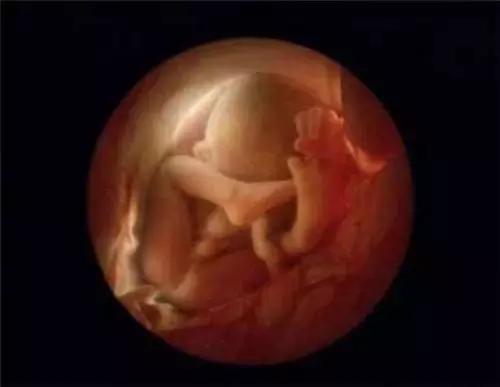

第8周

第10周。此时眼睑半闭,几周内会完全闭合

10周。胎儿已经可以使用双手来探索周围的环境